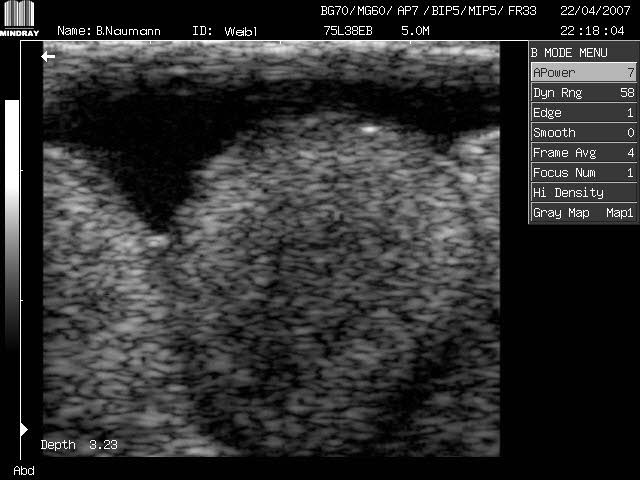

Contrôle manuel par Ultrasons